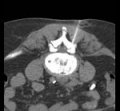

Under computer tomographic or magnetic resonance imaging control, drugs are injected with millimeter precision into the neuralgic points of the spine using fine injection needles. In many patients, this can result in significant pain relief or even freedom from pain. All pain therapy treatments can be carried out on an outpatient basis without any problems due to the low complication rates. A treatment takes a maximum of 10 to 30 minutes.

These interventions are CT-assisted, in which a thin special needle is positioned directly on the corresponding nerve plexus (neck, thorax, abdomen, or pelvis) under local anesthesia, and a mixture of local anesthetic and highly concentrated alcohol solution is injected locally. The alcohol solution leads to chemical obliteration of the nerve plexus and thus to pain reduction. The local anesthetic leads to immediate pain reduction when indicated and performed correctly and thus has diagnostic value. For this reason, the procedure is often performed in two stages.